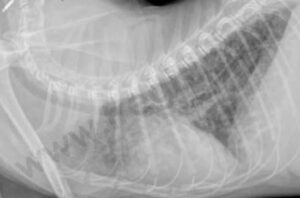

Péritonite infectieuse féline : modalités thérapeutiques

Péritonite infectieuse féline : modalités thérapeutiques from www.depecheveterinaire.com

Péritonite infectieuse féline - Centre Hospitalier ...

Péritonite infectieuse féline - Centre Hospitalier ... from www.fregis.com